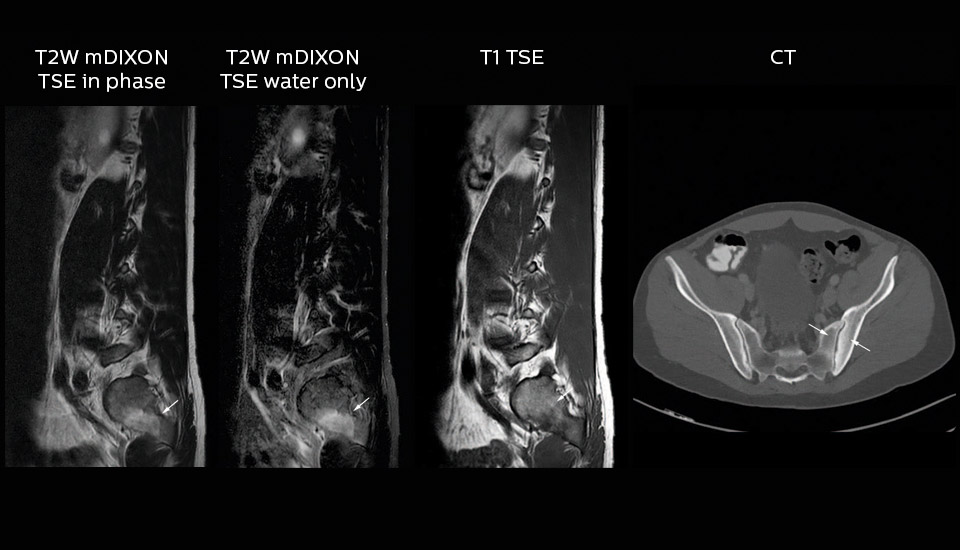

Dr. Heggelman raves about mDIXON TSE because it provides him an extra image series without having to add another scan. “With mDIXON TSE, we not only get a T2-weighted series, but we also get the T2 fat suppressed images ‘for free’ in the same scan. I feel much more confident with the homogeneous fat suppression that mDIXON TSE provides under virtually all conditions, even in this challenging anatomy. SPAIR and SPIR weren’t good enough due to the susceptibility problems in the air cavities, so that fat suppression was not homogeneous over the whole field of view. That made it difficult to see whether something was enhancing or the fat suppression was not good enough.”

“To me the most remarkable fact is that mDIXON TSE provides us T2-weighted images with and without fat suppression at the same time. In the past we needed two separate sequences for that, so it does save some time.”

“The excellent image quality of mDIXON helps us a lot. We can, for instance, see the foramina in the skull base very well. Also our confidence in imaging of the facial nerve and the trigeminal nerve is highly improved. Visualizing these nerves properly used to be difficult because they run very close to the air cavities. However, it is very important to know if there are abnormalities or not. I’m very satisfied with the possibilities of mDIXON TSE.”

mDIXON TSE also benefits MR imaging of orbits, according to Dr. Heggelman. “Using mDIXON TSE helps us reduce fat suppression problems due to susceptibility. The mDIXON TSE orbital images look outstanding. So, also here I get excellent fat suppressed images, and on top of that, the in-phase images as well in the same time.” “We can also use mDIXON TSE for post-contrast imaging and choose to have T1-weighted both with and without fat suppression at the same time. In the past, it took us two scans to get the same information!”